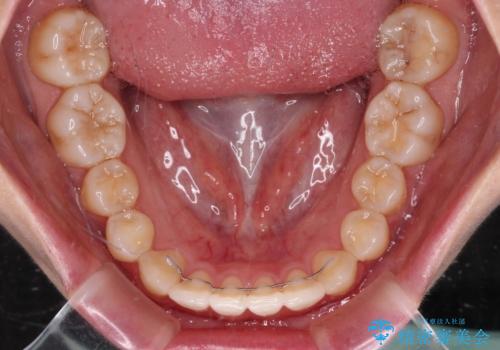

- 上顎前歯の隙間を気にして来院された患者様です。

下顎前歯が上顎前歯に食い込むような咬み合わせにより、上顎前歯が開いてしまっていたため、咬合高径の挙上により突き上げを改善するよう、インビザラインにより矯正治療を行うこととしました。

咬合高径の挙上により上顎前歯の突出感も改善することができ、整った口元となりました。